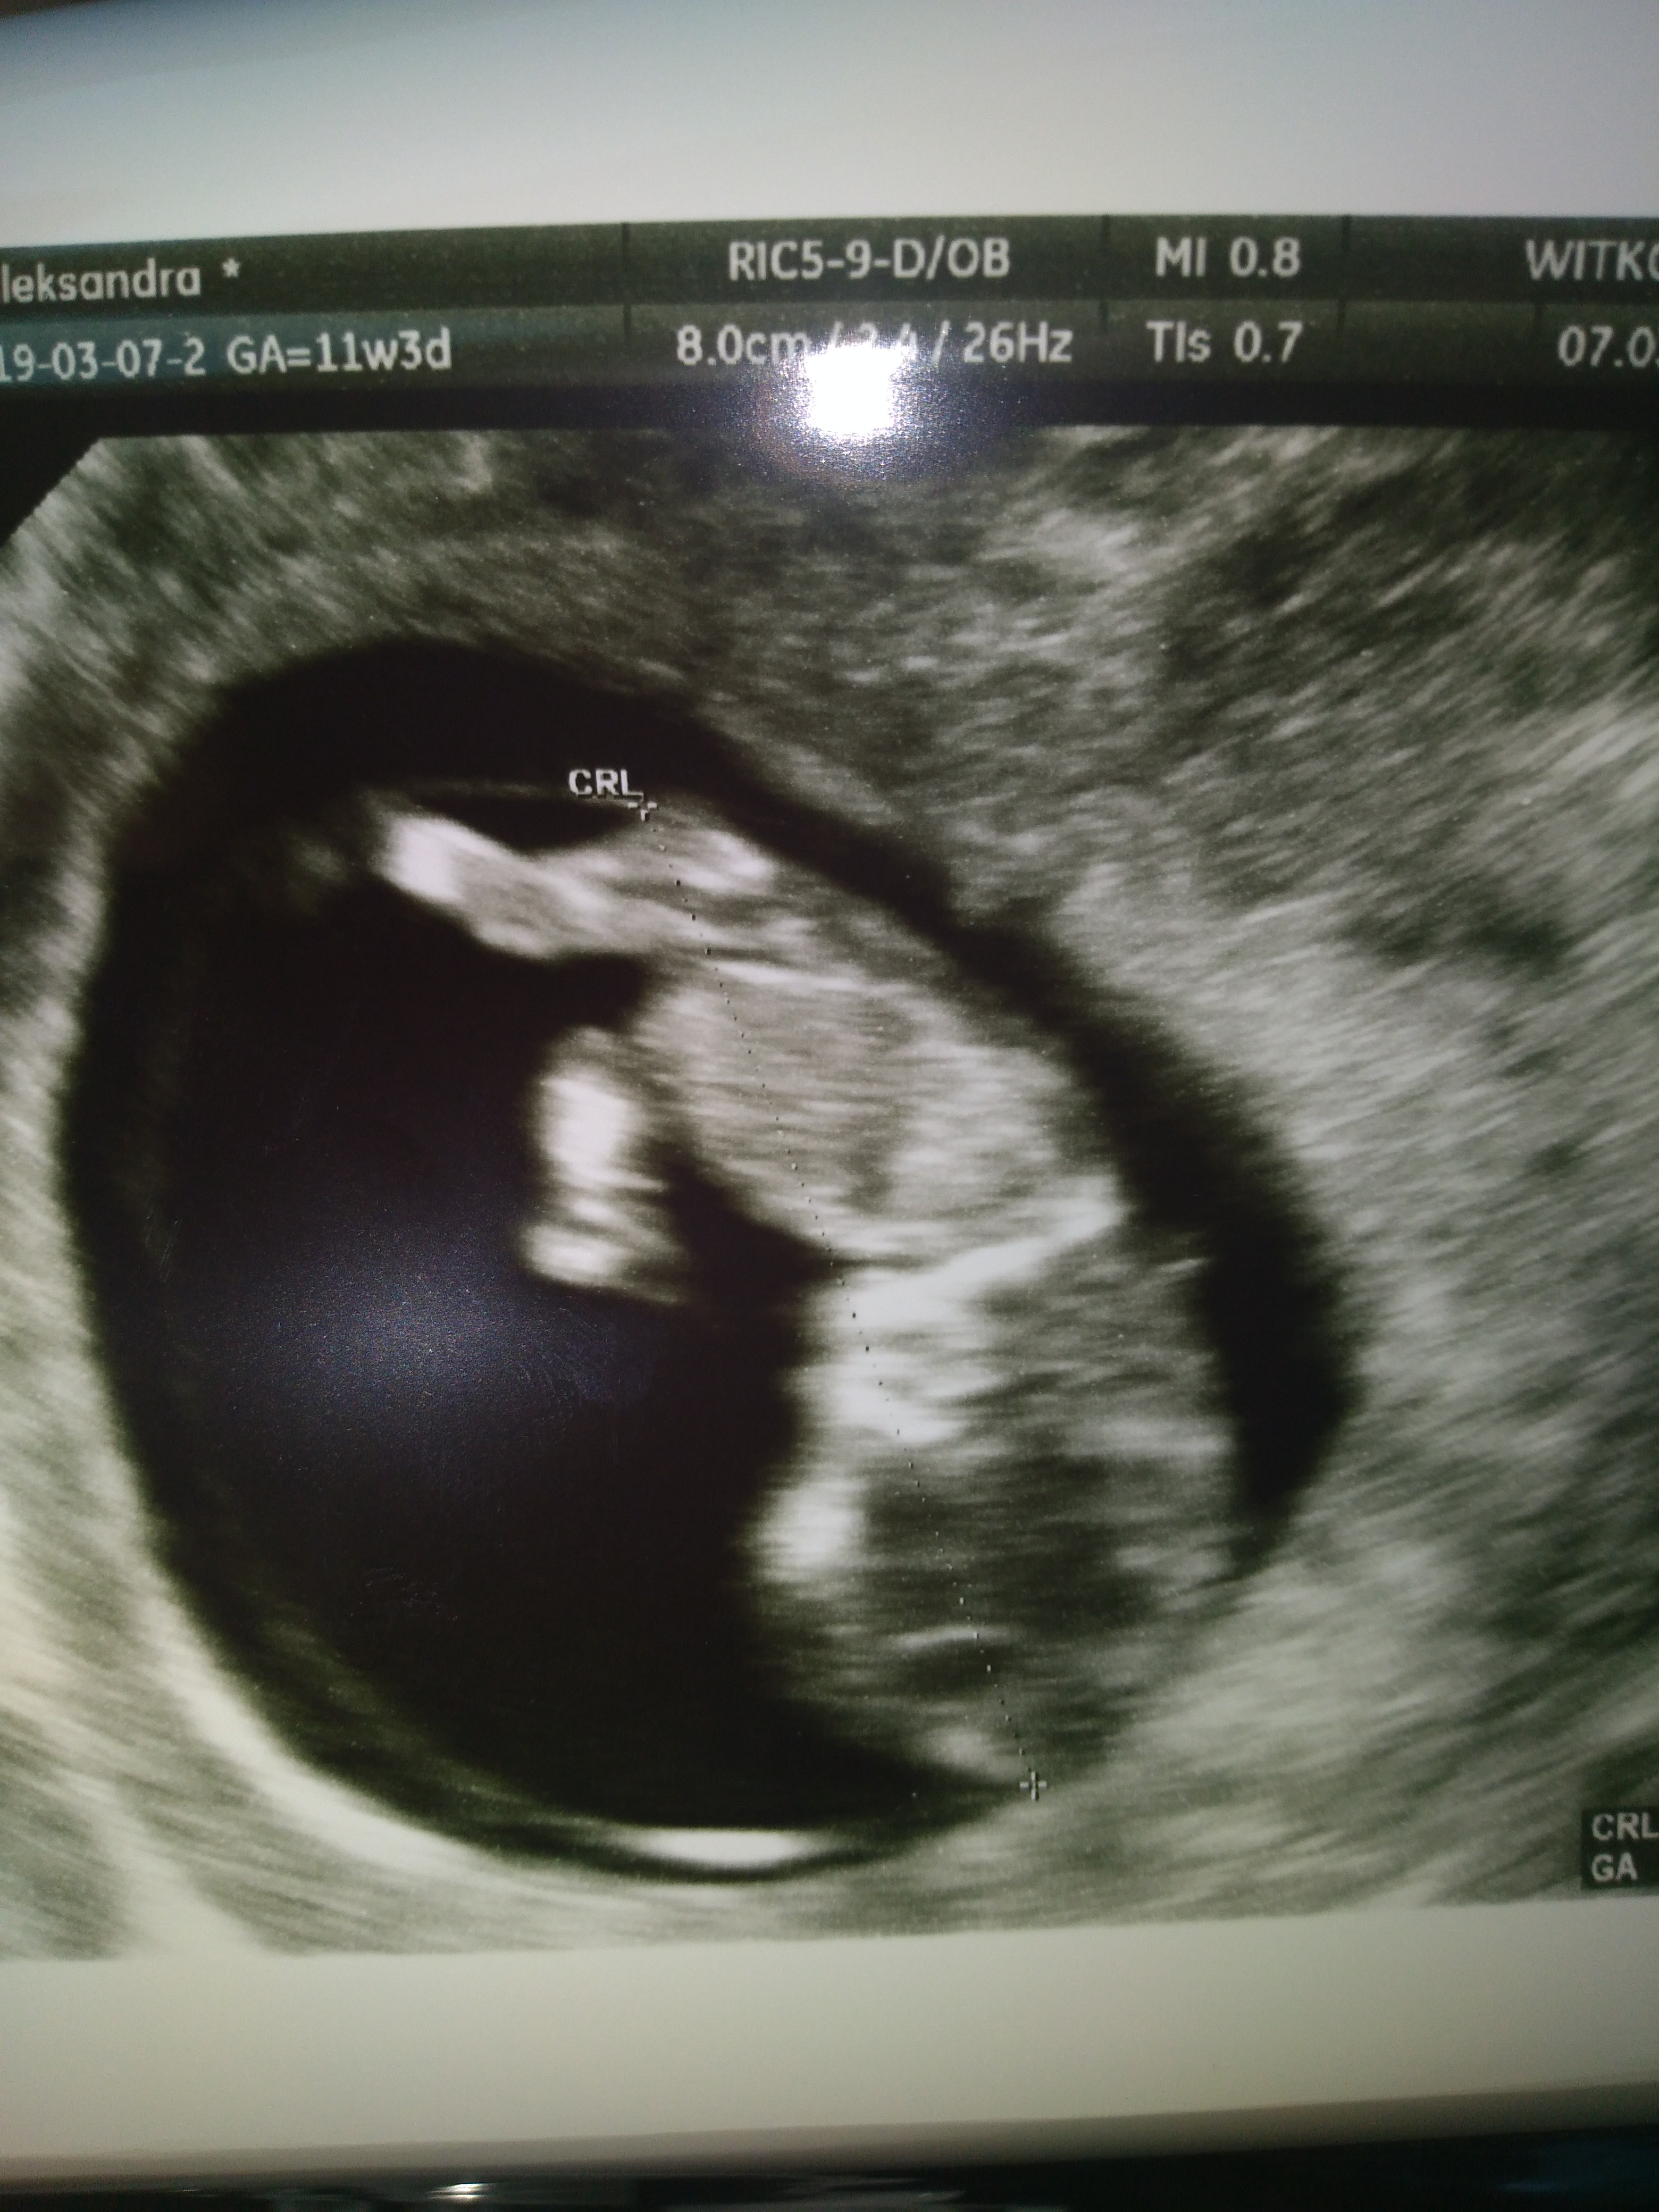

Nasze USG

07.03 :) crl 3,76